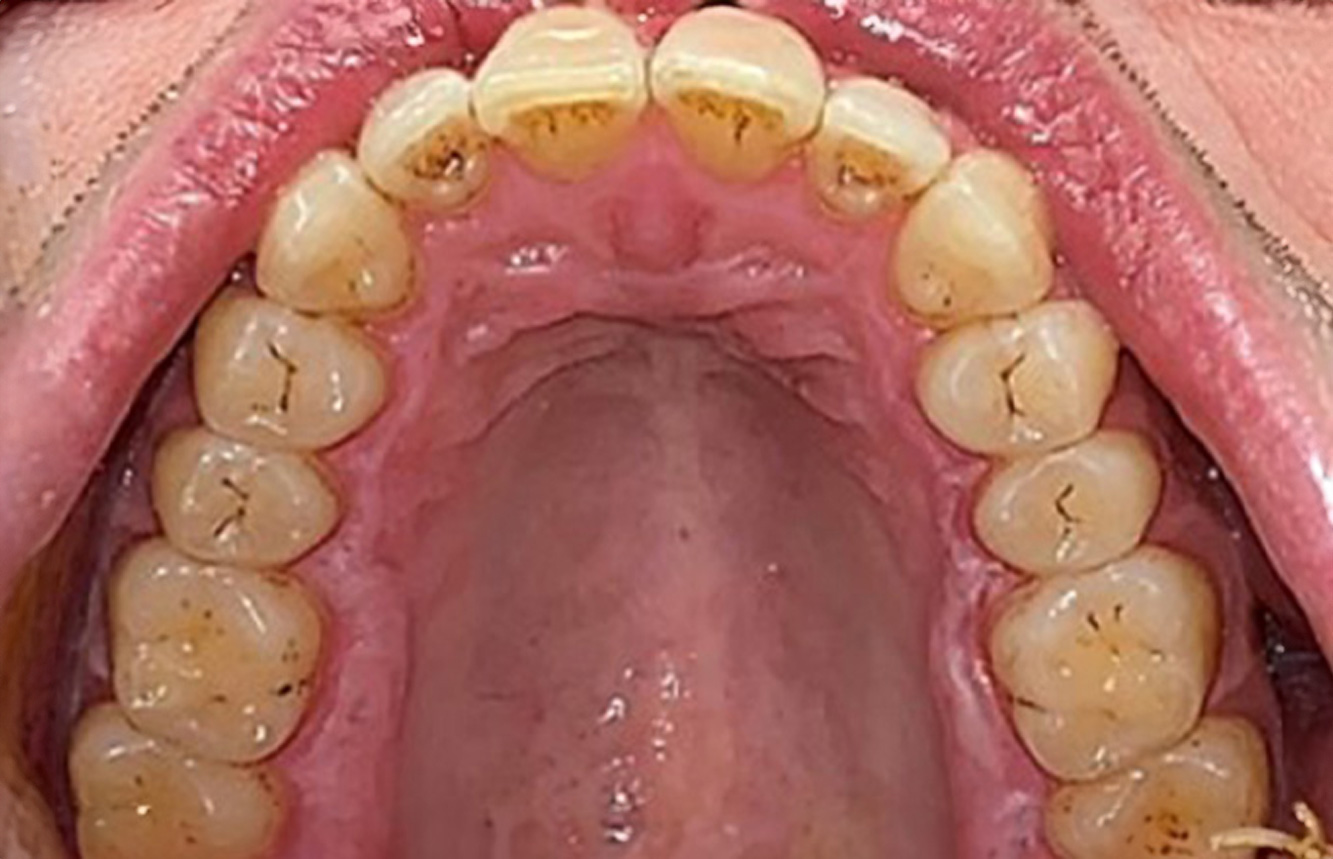

Fallpräsentation: Management komplexer Zahnprothetik

Es ist längst bekannt, dass Mundgesundheit und Allgemeingesundheit in direktem Zusammenhang stehen und einen zum Teil bidirektionalen Einfluss aufeinander haben. Die Berücksichtigung beider Faktoren sind bei der Planung der oralen Prävention und Therapie der Patienten in der Zahnarztpraxis unabdingbar. Dabei ist oberstes Ziel, die Gesundheit und die Lebensqualität der Patienten sowohl aus zahnmedizinischer -und medizinischer Sicht zu erhalten. mehr Infos